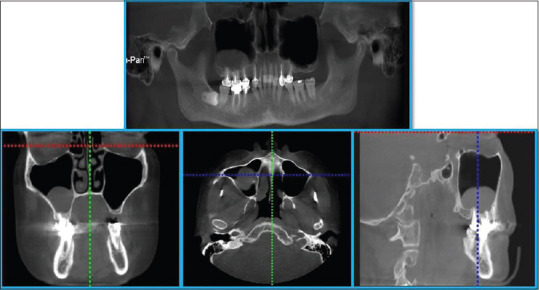

Abstract Image